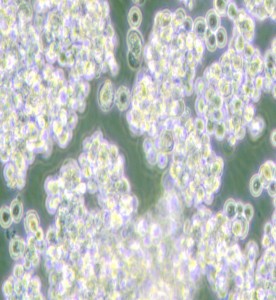

NCI-H524人小細胞肺癌細胞

中文名稱 : 人小細胞肺癌細胞

細胞簡稱 : N CI-H 524

細胞形態 : 圓形

生長特性 : 懸浮細胞